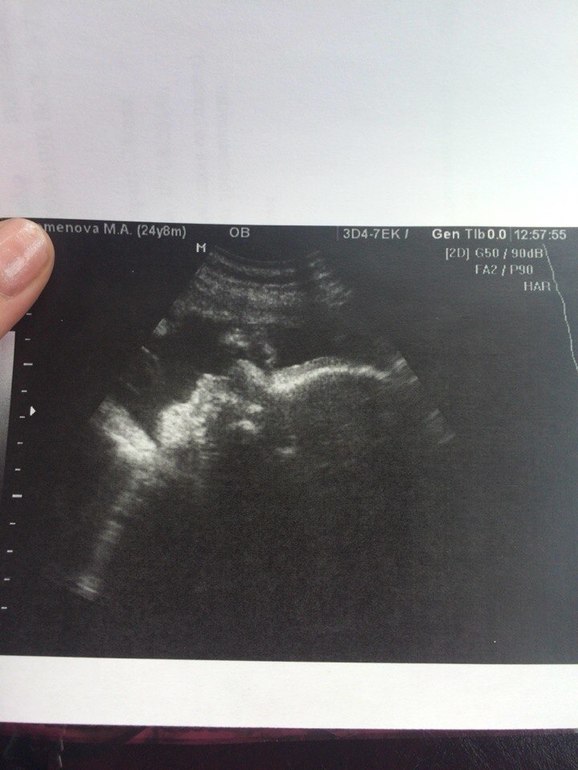

Моя печенюха уже 40 см и 2068гр! Правда, закрыла личико кулачками, и не дала нам толком ничего рассмотреть) Зато уже с прической! Сказали после РД сразу в парикмахерскую

Обвития нет, головное предлежание, что не может не радовать) СБ 146 уд/мин., плацента 1 степени зрелости.